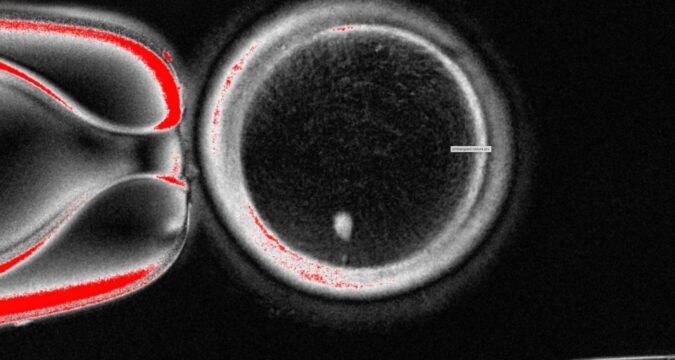

The OHSU team removed the nucleus from a human egg cell and replaced it with the nucleus from a human skin cell. But a skin cell contains two sets of chromosomes, and eggs and sperm are supposed to each contain only one set that combine during fertilization. The researchers therefore induced the egg-like cells to discard extra chromosomes, injected donated sperm and jumpstarted post-fertilization development.

About 9% lasted for six days in lab dishes, reaching the blastocyst stage of early embryo development, before the experiment was stopped.